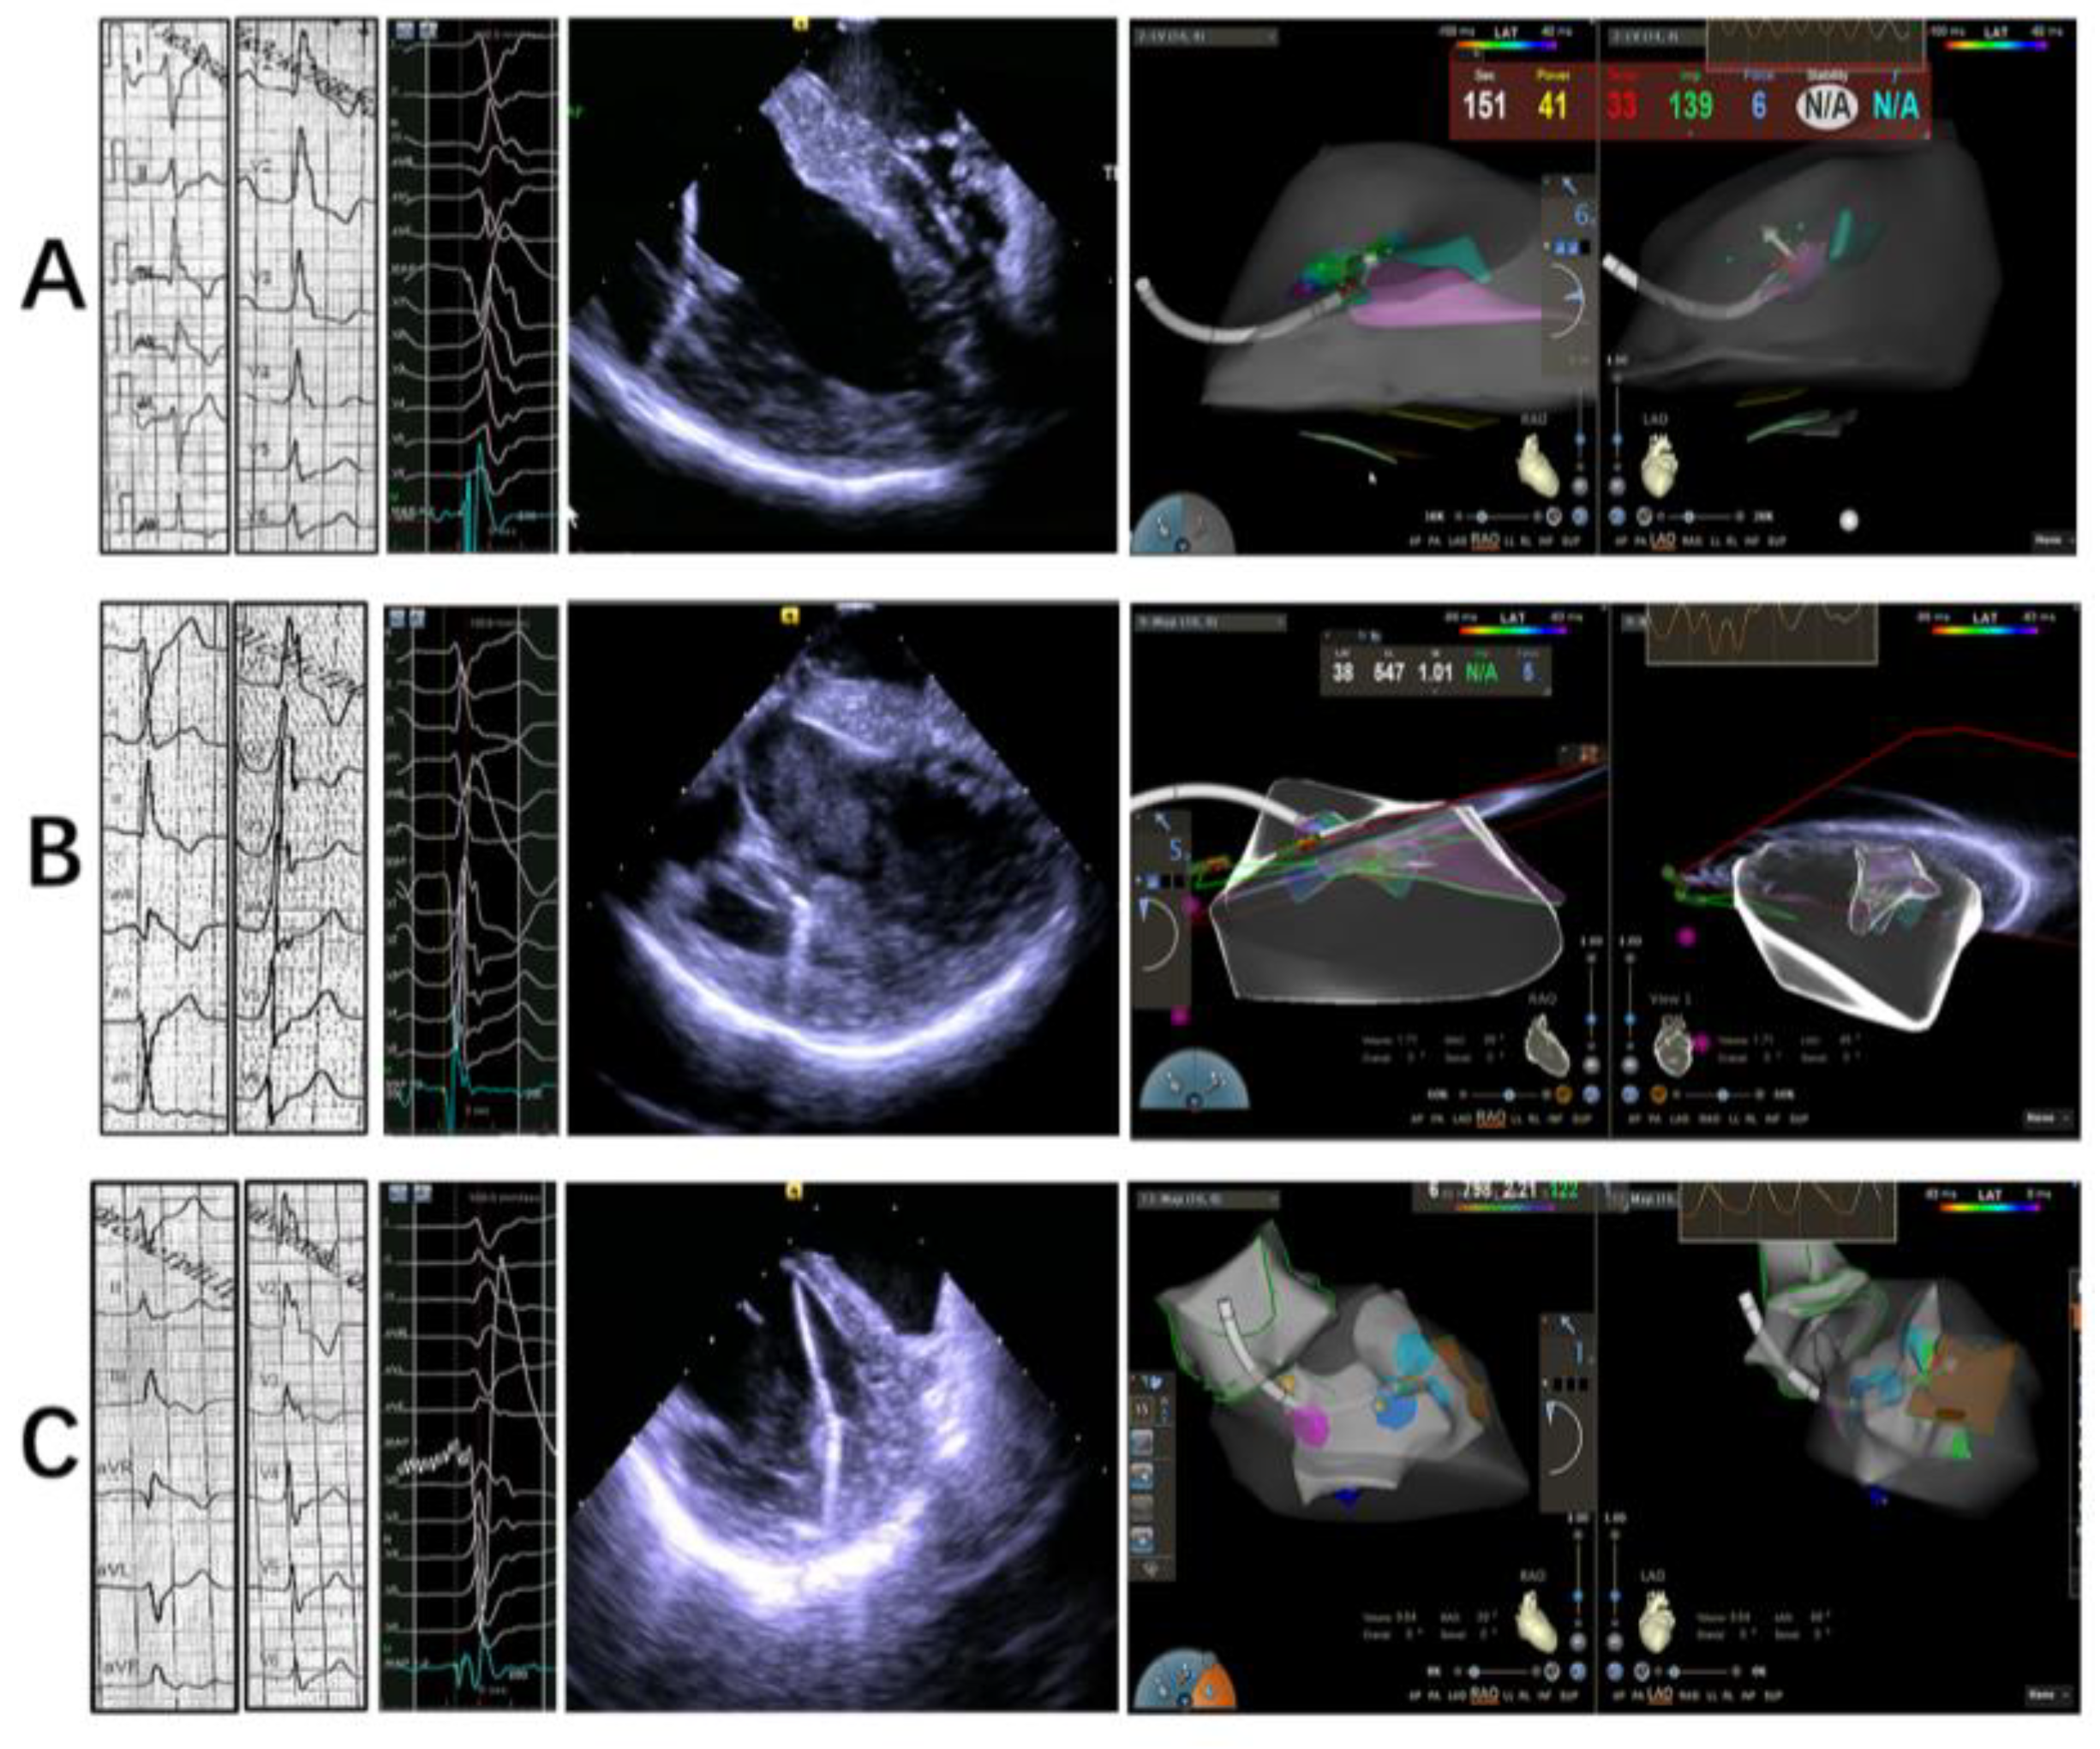

2.2. Electrophysiology Study, Mapping and Ablation

2.2.1. Intracardiac Echocardiography

2.2.2. Mapping and Ablation

4.1. Integration of Echocardiography and 3D Mapping

4.2. Contact Force